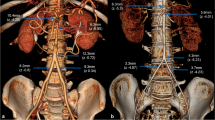

Aortic diameter

Modelling aortic diameter and growth

We designed a forecasting model, allowing prediction of changes in aortic diameter over time. This model was flexible, and allowed use in two versions. In one version, modelling can be performed without knowledge of prior aortic imaging and on the basis of other accessible data such as body surface area, blood pressure, and aortic valve status. In another version, baseline or even follow-up measurements of the aorta may be entered in addition to other risk factors. Not surprisingly, the accuracy of the modelling improved with the use of multiple aortic measurements. The prediction model also highlighted that it is possible to categorise females with TS into low and high risk for more or less rapid aortic dilation based on a number of risk parameters present, such as previous measurement of the aorta. In Figure 2A, 2C and 2E we present data from three females at different ends of the risk spectrum, running their data through the model. The figures demonstrate that risk factors additively predict progressive aortic dilation over time, especially in the ascending aorta, and that aortic growth primarily takes place in the ascending aorta closest to the aortic valves. Some females displayed growth according to prediction while others demonstrated rapid growth of the aorta exceeding the boundaries of the prediction limits of the model (Figure 2B, 2D and 2F), and we speculate that such individuals should be considered for more targeted medical or surgical intervention [9].

Mathematical modelling of aortic diameter in Turner syndrome with varying burdens of risk factors for aortic complications, aiming to validate the predictive models against actual data collected in three real patients. Aortic measurement position (nine: from aortic sinuses to descending thoracic aorta) is depicted on the x-axis. A) Perceived low risk burden: 26-year old, tricuspid aortic valve, no aortic coarctation, ambulatory blood pressure (ABP) 104/66 mmHg, body surface area (BSA) 1.46 m2, and karyotype 45,X (dots: actual measurement at baseline; full black line: prediction at baseline from modelling of the complete cohort (n = 102); dotted lines: 95% prediction limits). B) Same low-risk female (as in A) (dots: actual measurement at 4 years; full black line: 4 year prediction; dotted lines: 95% prediction limits; full red line: prediction at 8 years from baseline). C) Perceived high risk burden: 49-year old, bicuspid valves, aortic coarctation, hypertension (ABP 124/67 mmHg during antihypertensive treatment), BSA 1.60 m2, and karyotype 45,X/46,X,r(X) (dotted line: actual measurement at baseline; full line: prediction at baseline; dotted lines: 95% prediction limits). D) Same high-risk female (as in 2C) (dots: actual measurement at 4 years; full black line: 4 year prediction; dotted lines: 95% prediction limits; full red line: prediction at 8 years from baseline). E) Perceived high risk burden: 43-year old, bicuspid valves, no aortic coarctation, diagnosed hypertension (ABP 143/90 mmHg during antihypertensive treatment), BSA 1.47 m2, and karyotype 45,X (dotted line: actual measurement at baseline; full line: prediction at baseline; dotted lines: 95% prediction limits). F) Same high-risk female (as in E) (dots: actual measurements at 4 years; full black line: 4 year prediction; dotted lines: 95% prediction limits; full red line: 8 yeard prediction), and please note that ascending aortic measurements fell outside the prediction. Please also see http://www.biostat.au.dk/MERL/Aorta_Prediction_model.htm.